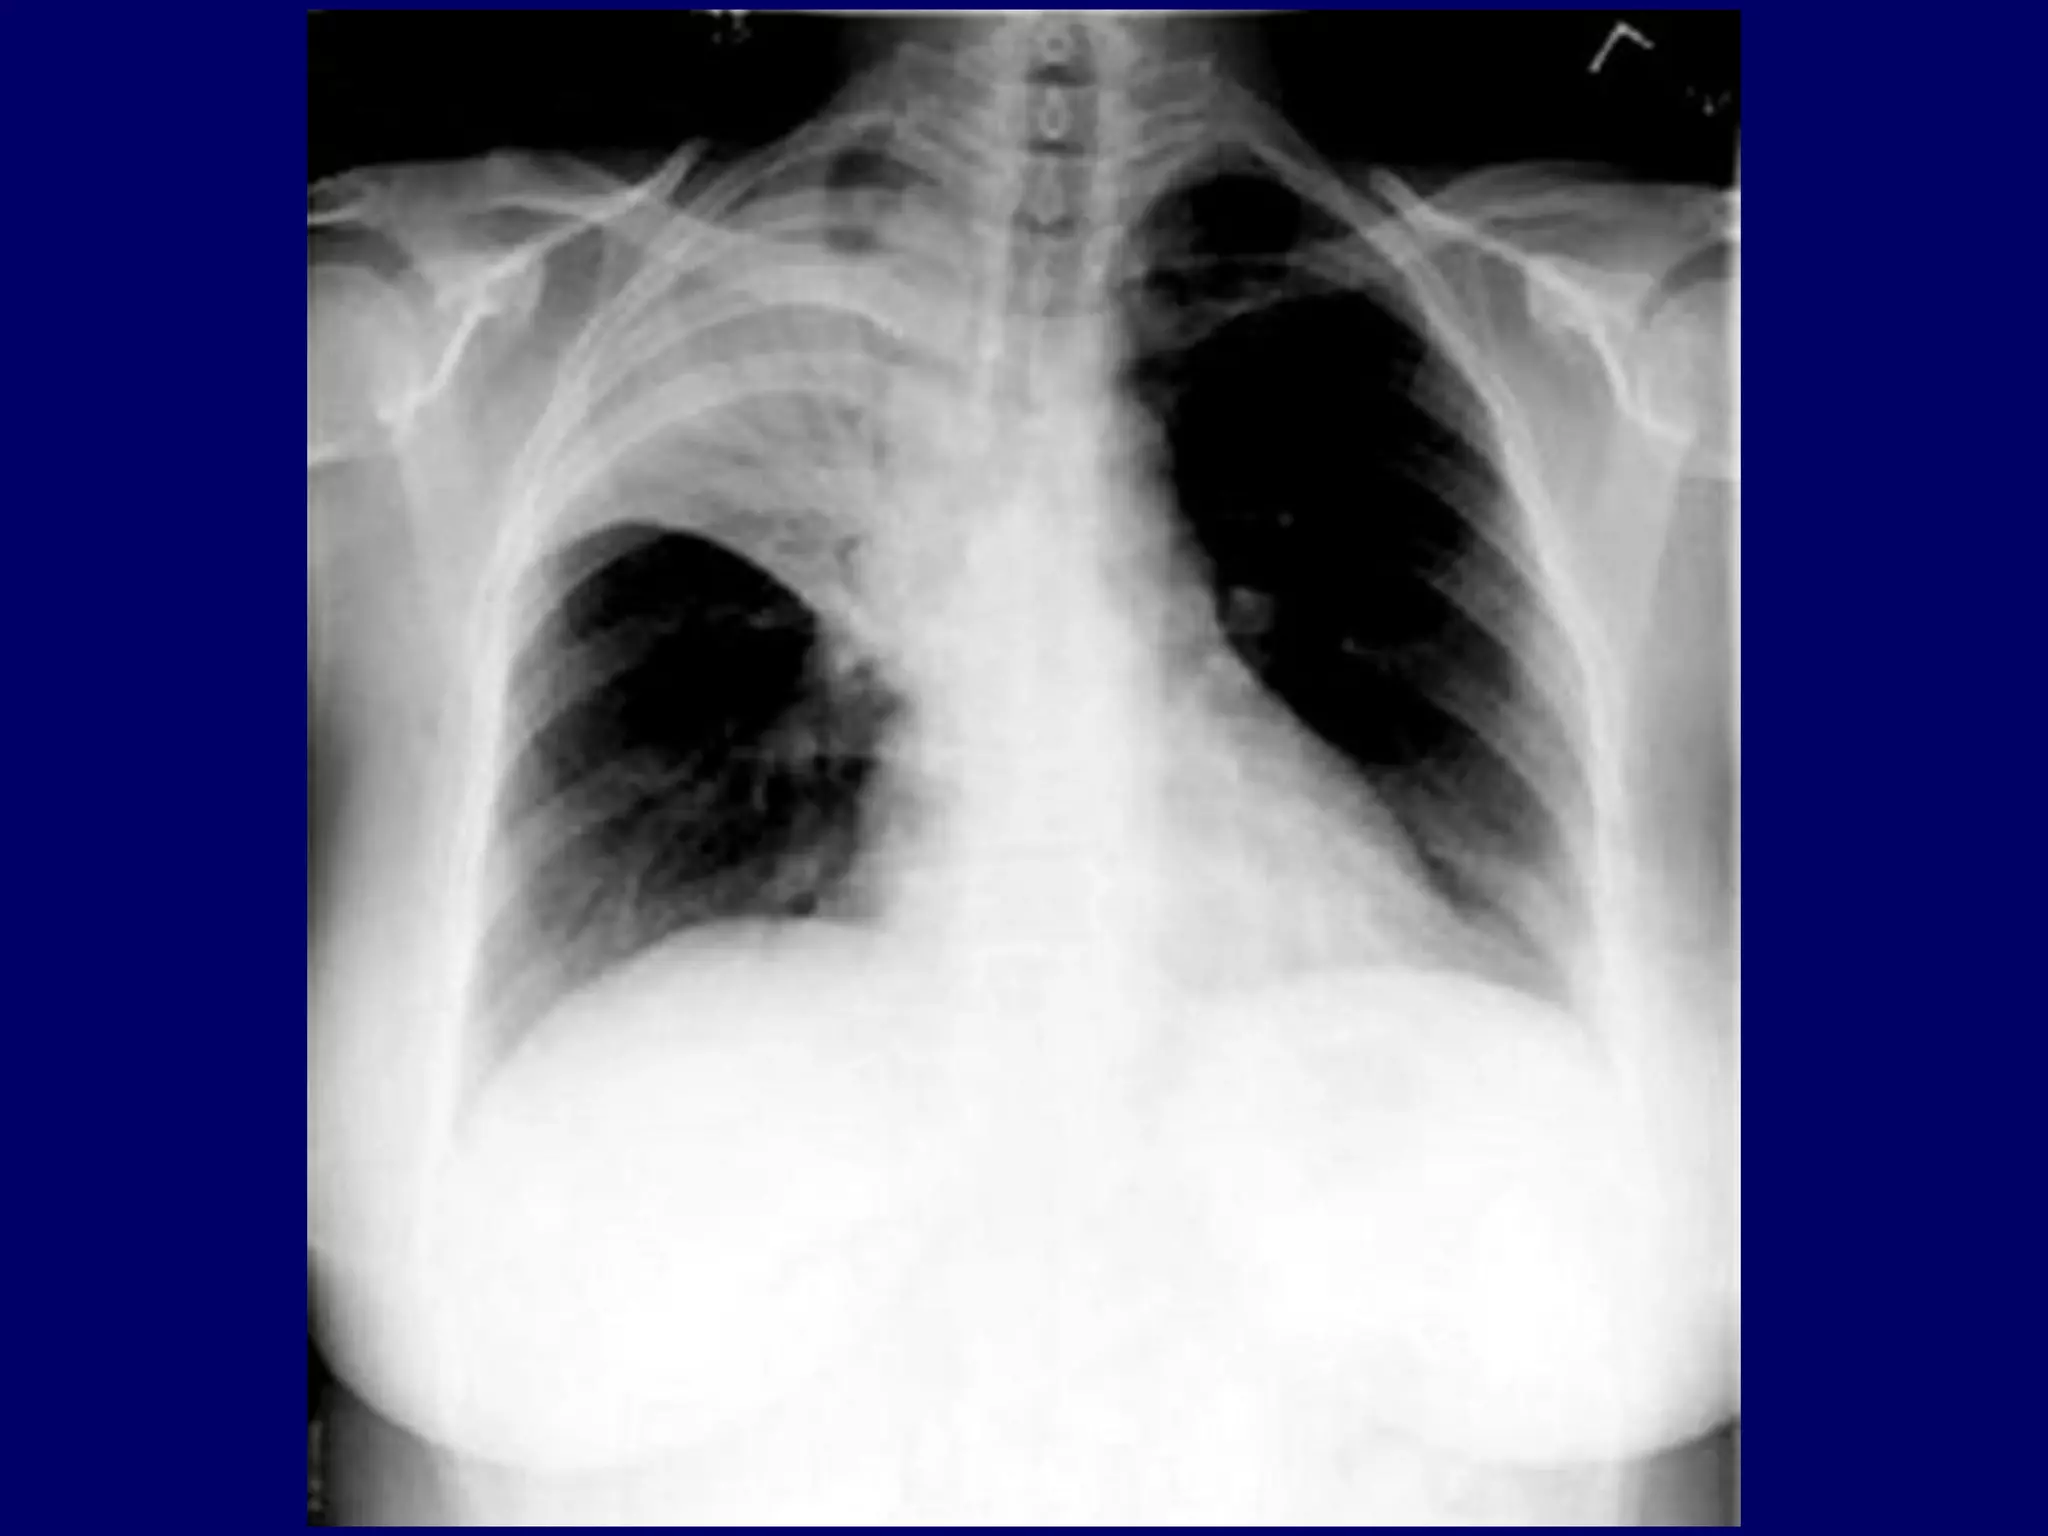

Sub-segmental Atelectasis

Atelectasis

Segmental

Anterior sub-segment of RUL

"Bronchial wedge"